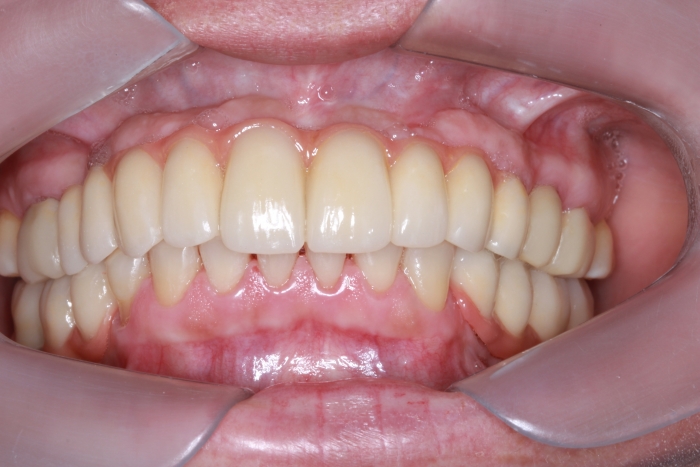

Sorriso Final